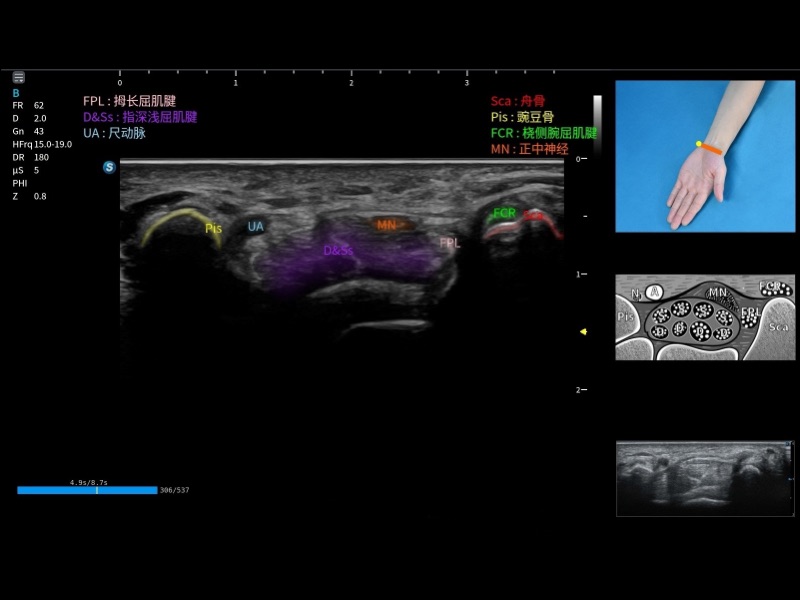

指导操作者进行标准切面的正确扫查,涵盖丰富应用场景,为新晋医生提供实用的参考指导。

将测量、体标和注释等关键内容整合到一个页面中。精简界面,诊断更有针对性。

可助力简化工作流程,同时提升操作标准化程度,并减少按键次数,缩短检查时间。